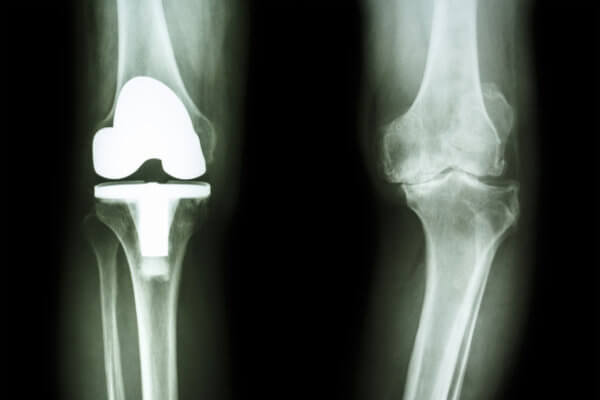

Η αρθροπλαστική αντικαθιστά μια φθαρμένη άρθρωση με εμφύτευμα, με στόχο την απαλλαγή από τον πόνο και την αποκατάσταση της κίνησης.

Με τη χρήση παθητικού ρομποτικού πλοηγού εξασφαλίζεται απόλυτη ακρίβεια στην τοποθέτηση των εμφυτευμάτων και στην ισορροπία των μαλακών μορίων, ενώ παράλληλα εφαρμόζονται τεχνικές ελάχιστης επεμβατικότητας που μειώνουν τον μετεγχειρητικό πόνο και επιταχύνουν την κινητοποίηση, οδηγώντας σε φυσικότερη κίνηση, καλύτερη κινητικότητα και μακροχρόνια αντοχή.